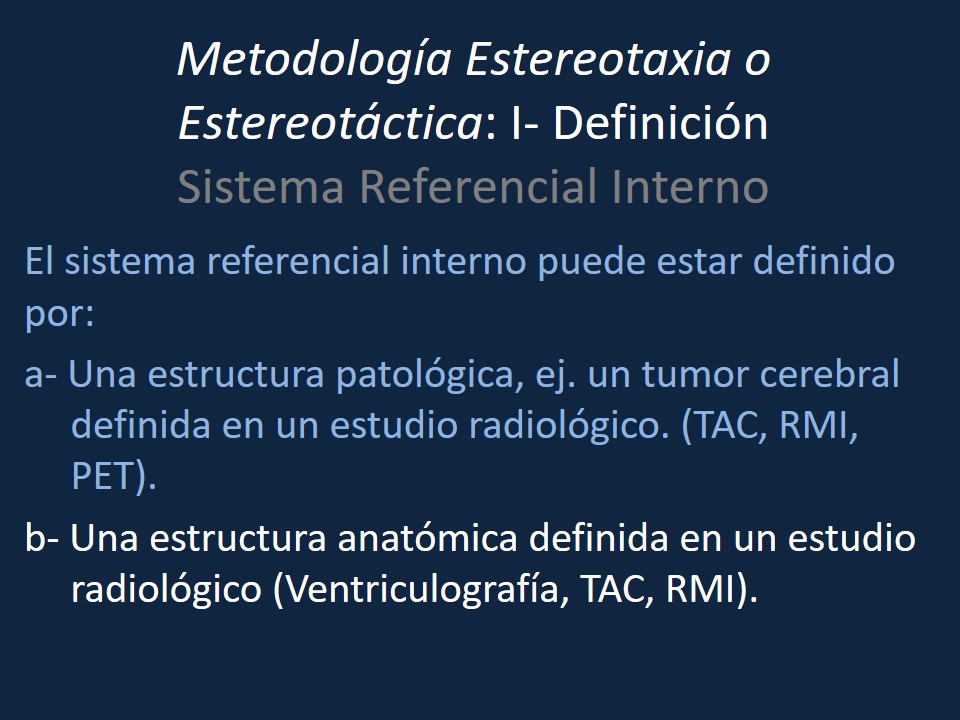

Metodología Estereotáctica o Estereotaxia